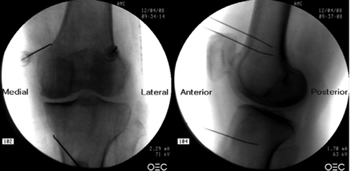

Fluoroscopy-guided genicular nerve radiofrequency

To perform a fluoroscopic-guided TRFGN, we need an anteroposterior (AP) and lateral view of the knee (Figure 2). First we place the patient in supine position with a pillow under the popliteal fossa (to make the patient more comfortable) (16). After performing asepsis and antisepsis of the knee, we proceed to locate the GN (Table II). SLGN is advancing the TFR needle toward the confluence of the lateral femoral diaphysis with the lateral femoral condyle in an AP view and at a mid-point of the femur in a lateral view. The SMGN is located by advancing the needle toward the confluence of the medial femoral diaphysis with the medial femoral condyle in an AP view and at a mid-point of the femur in a lateral view. Finally, the IMGN is located by advancing the needle toward the confluence of the medial tibial diaphysis with the tibial epicondyle in an AP view and at a midpoint of the tibia in a lateral view (16,17).

Fig. 2. Anteroposterior (AP) and lateral projection where therapeutic targets are observed using fluoroscopy. Image taken from Choi et al. (9). Reproduced with the permission of Jin Woo Shin.

Table II. Location of genicular nerves guided by fluoroscopy

Good AP and lateral view is very important. In AP projection, the tibiofemoral joint should have a similar width on both sides of the knee with the interspace open (9). In lateral projection, there must be a correct overlap of both femoral condyles to perform a satisfactory blockage of the SMGN and SLGN (18).